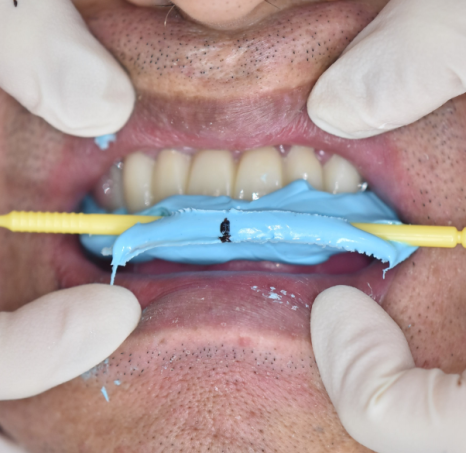

그동안은 임시 틀니로 식사가 가능하게 해드렸고요

임플란트가 뼈와 붙을 때까지

치료할 수 있는 치아 먼저 치료하였습니다.

하악 전체 임플란트 치료였기에 높이를 재건해주는게 중요했습니다.

임시치아 과정도 거치고